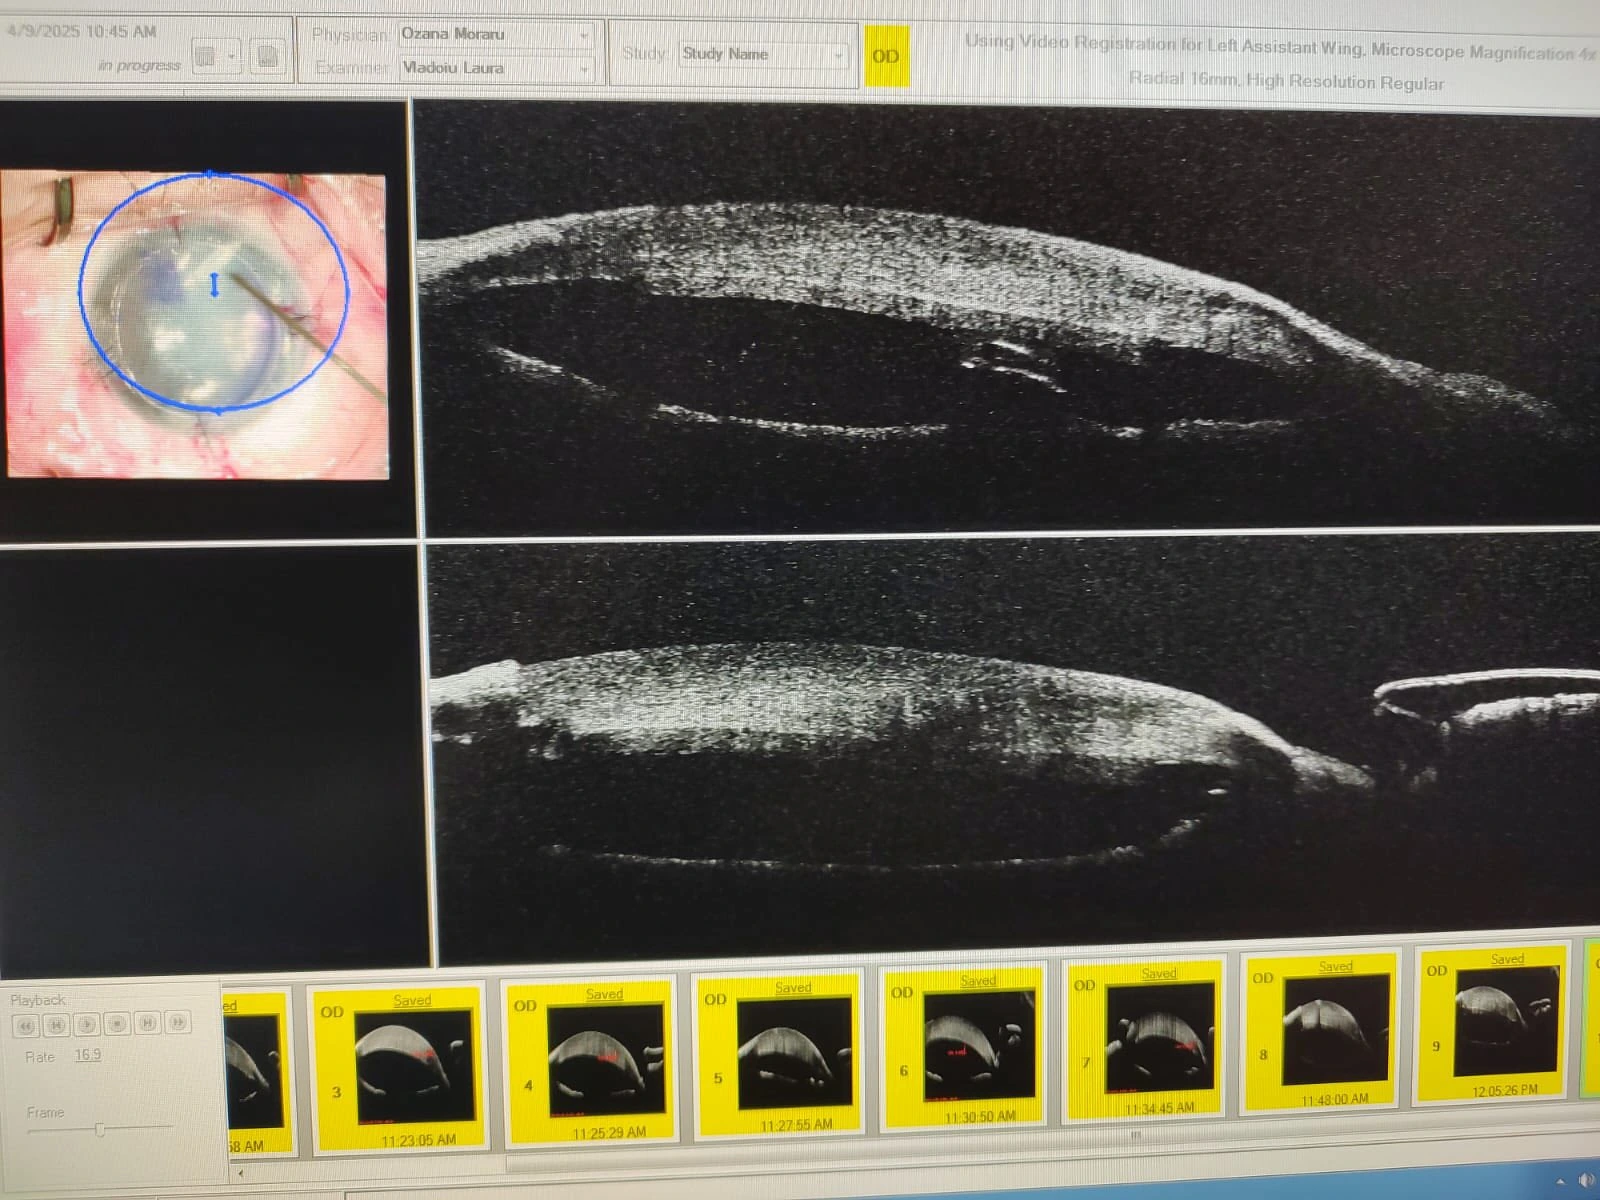

Singurul tratament eficient este un transplant de cornee – de dorit, un transplant   lamelar posterior DSAEK sau DMEK, deoarece acesta se vindecă mai repede, cu recuperarea mai rapidă a vederii finale. Asemenea intervenții au loc la Clinica Oculus în fiecare săptămână – mai precis, în fiecare zi de miercuri – iar ziua de azi nu a făcut excepție: azi am avut două cazuri de transplant DSAEK, ambele pentru keratopatie buloasă. Unul dintre ele a reprezentat un caz special: o cornee extrem de groasă (peste 1600 de microni), la un ochi operat de cinci ori de glaucom, de la trabeculectomie, la shunt-uri ExPress, implantate, ulterior parțial extrase, până la valve de drenaj, implantate, ulterior una extrasă etc.

Toate aceste patologii asociate cresc dificultatea operației și limitează prognosticul, dar noi sperăm într-o evoluție foarte bună nu doar intraoperatorie, ci și postoperator pe termen mediu și lung!